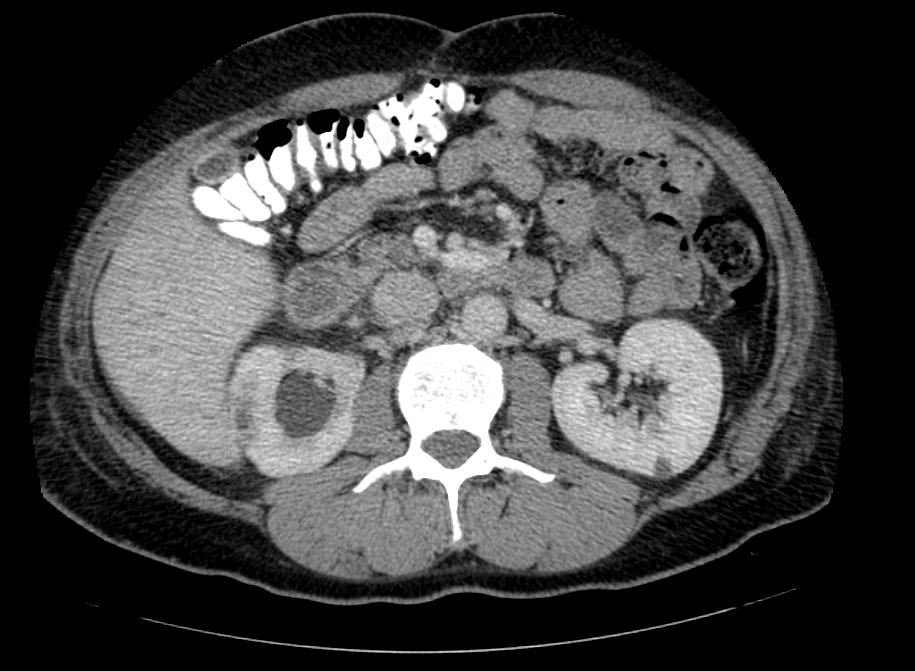

Фотографии и снимки КТ легких без контрастных веществ

Раздел: Визуальный дайджест